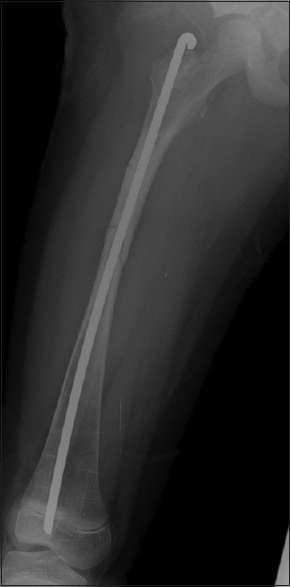

Background: Corrective osteotomy and intramedullary rodding are widely used in children with osteogenesis imperfecta (OI), but revision rodding is often required. This study aims to investigate the effect of purchasing distal femoral epiphysis on the longevity of fixation using non-elongating rod.

Methods: We investigated children with Sillence type III or IV OI who received antegrade femoral Rush rod fixations at age between 4 and 10 years in our institution. The fixations were classified into group A in which the rod reached distal femoral epiphysis and group B in which the rod stopped at femoral metaphysis. Failure of fixation is defined as rod cutting out of the cortex or when revision surgery was performed. Calculation of longevity of each rod fixation and Kaplan-Meier survival analysis were performed and compared between the two groups.

Results: Eighteen children had the first femoral rodding at a mean age of 6.9 years and received a total of 61 femoral roddings with a mean follow-up of 11.4 years. Group A included 38 roddings performed at a mean age of 7.1 years and group B included 23 roddings performed at a mean age of 6.6 years. Group A had less revision rate (58% vs. 87%), more chance of survival > 3 years (74% vs. 43%), and longer median survival time (80 months vs. 33 months) than group B.

Conclusions: Less revision rate and better 3-year and 5-year survival rate were proved in the roddings that purchased epiphysis. We emphasize on using the precise implant length to purchase distal femoral epiphysis when non-elongating rod is the only available implant for fixation in children with OI.